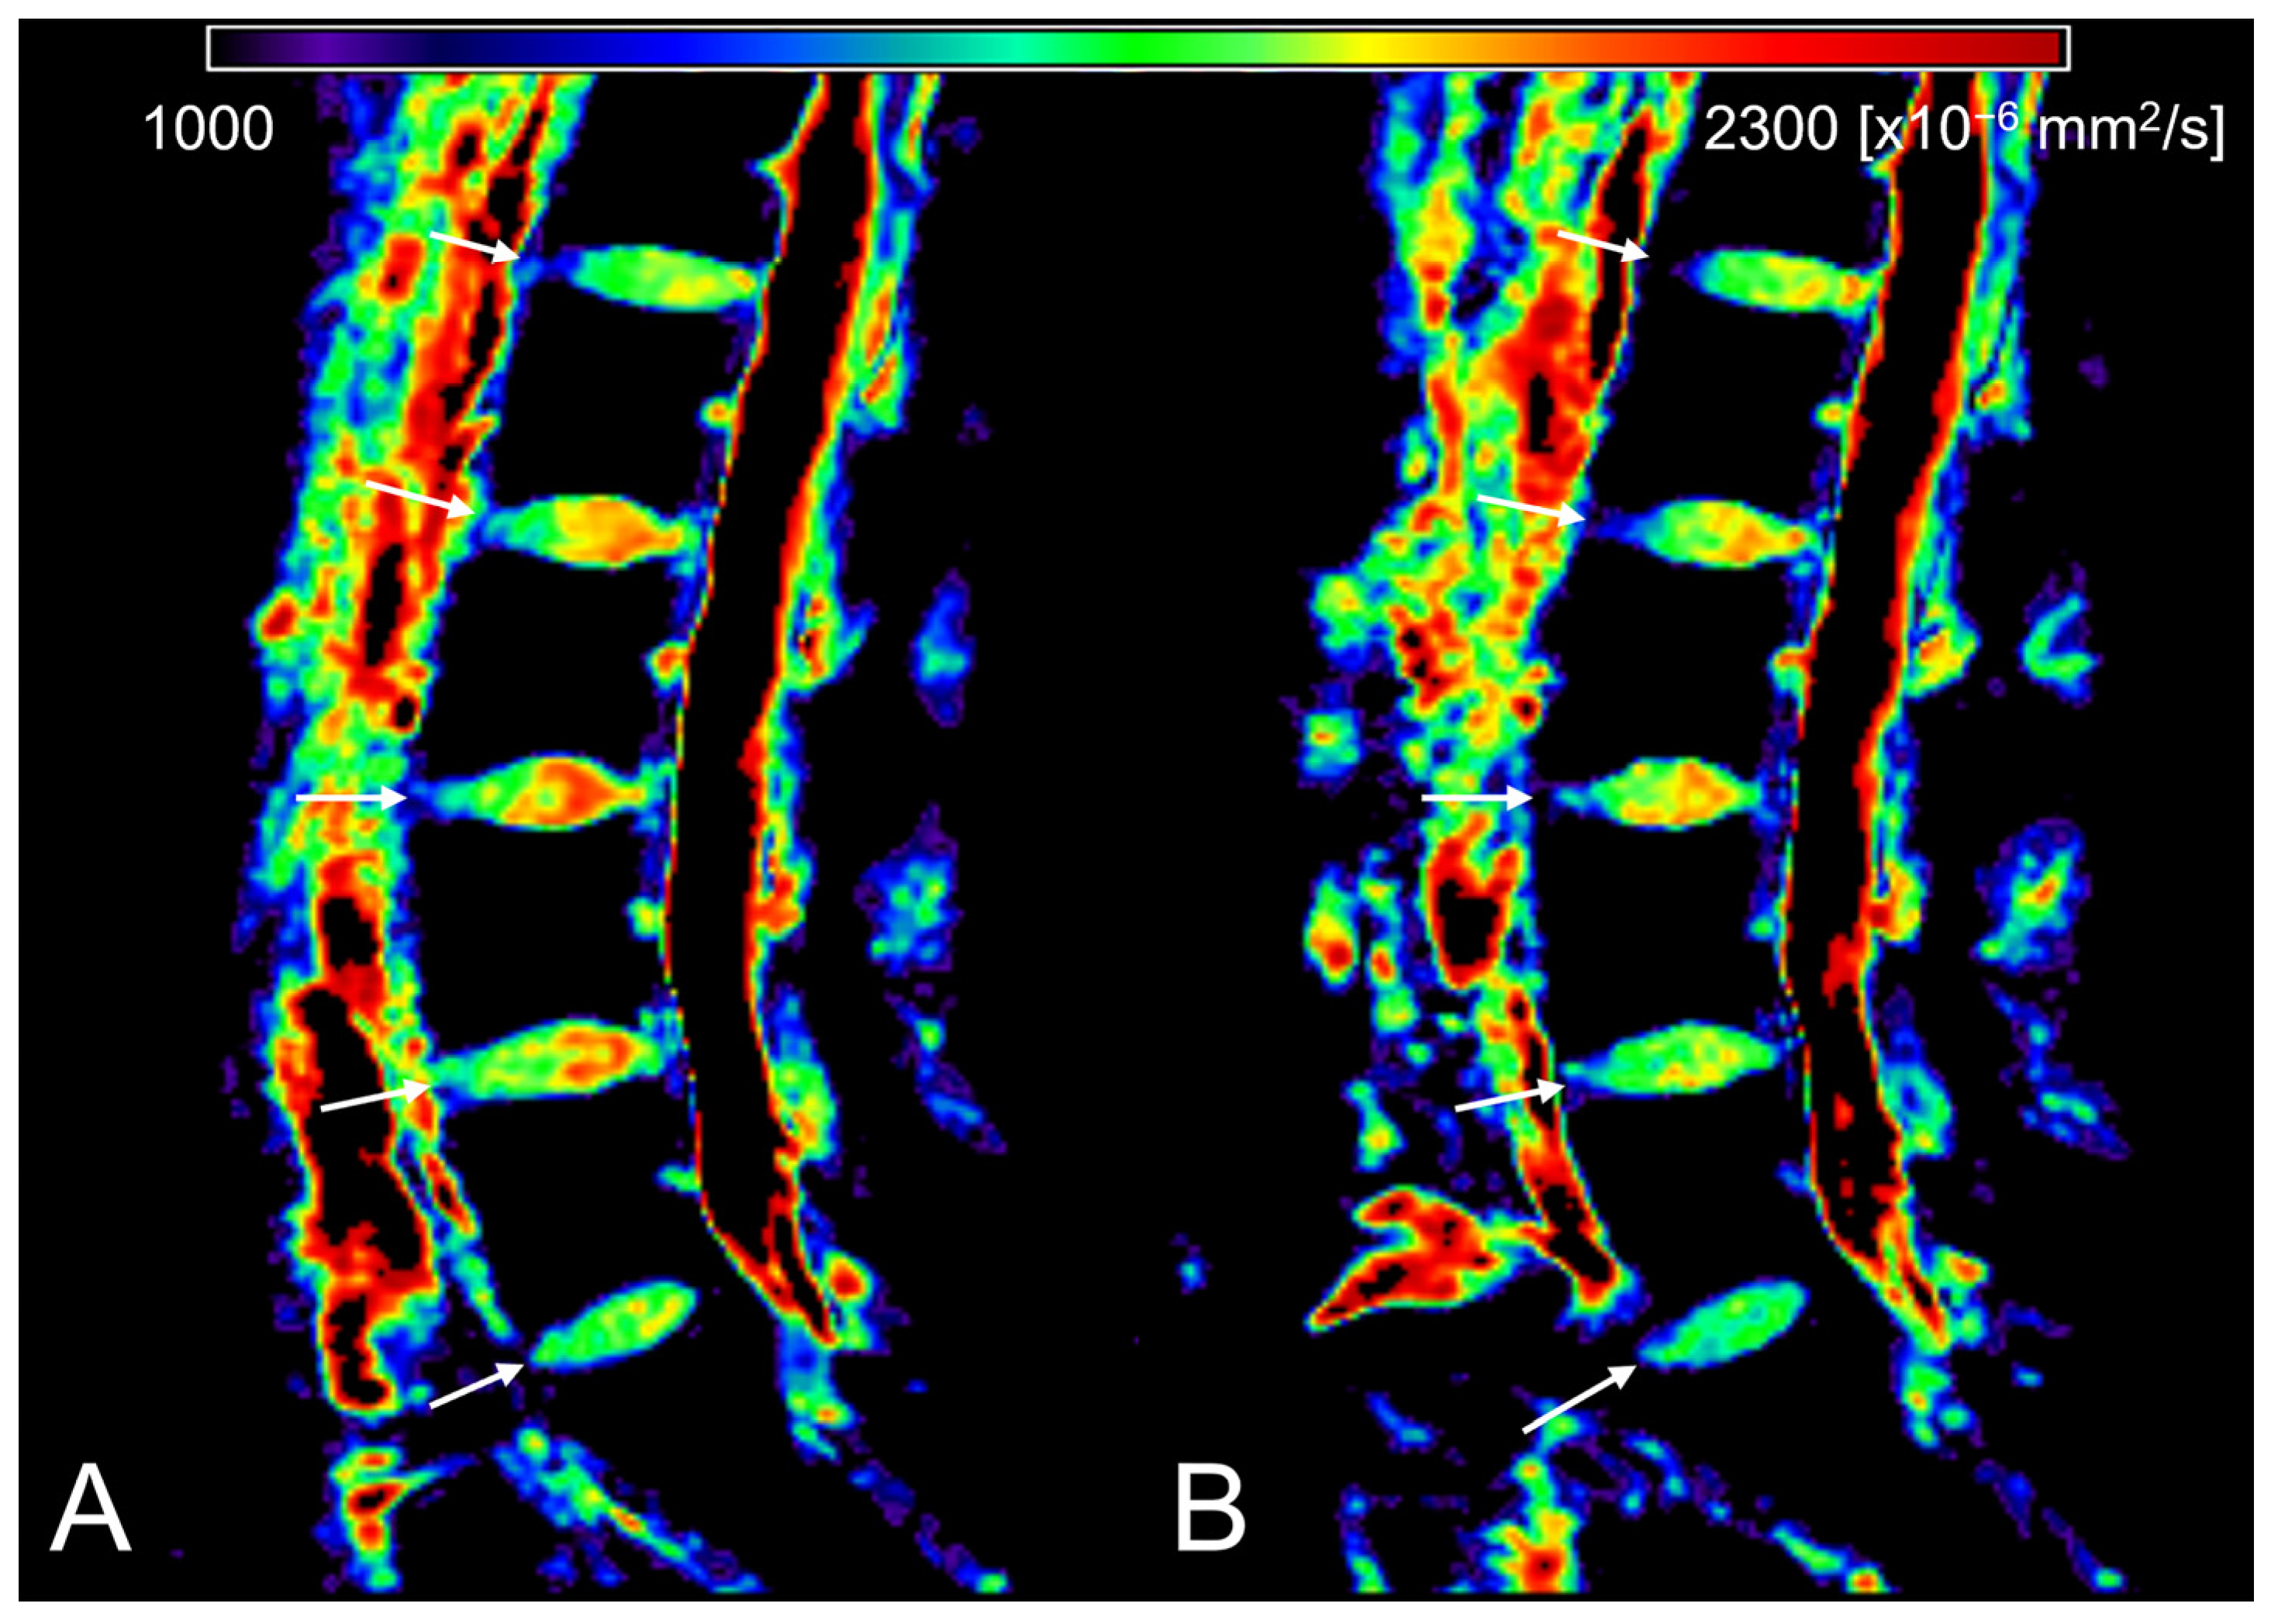

2.5. Region-of-Interest Setup and Measurements